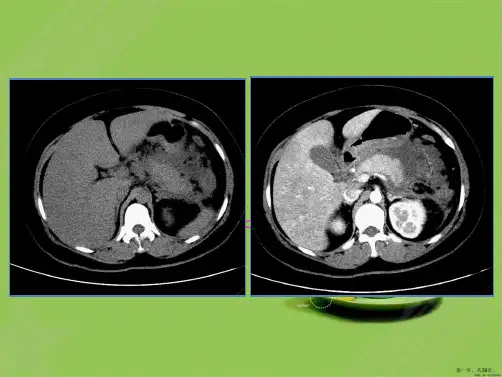

急性胰腺炎(acute pancreatitis,AP)是胰腺的急 性炎症和细胞损害过程,在不同程度上波及邻近 组织和其他脏器系统。导致胰腺组织自身消化、 水肿、出血甚至坏死的炎症反应。